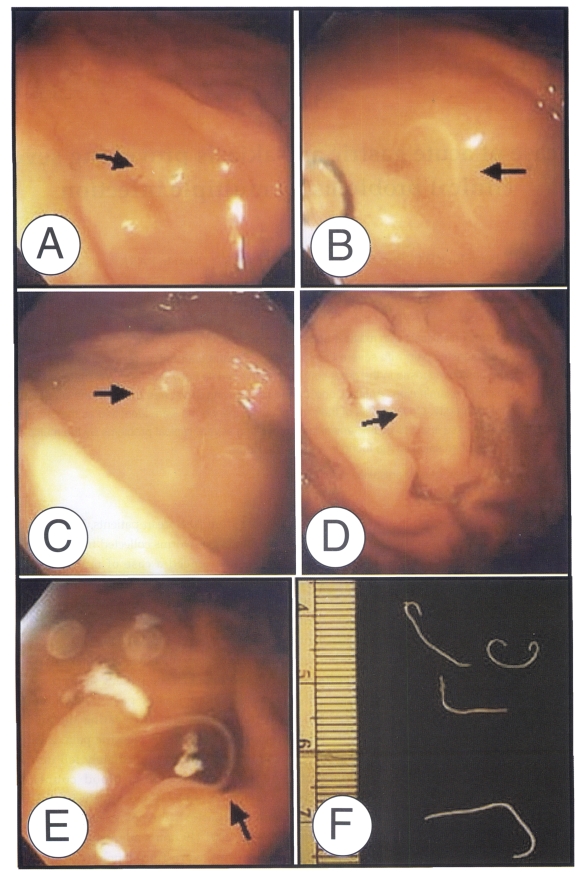

A 68-year-old Korean woman, residing in Busan, Korea, was admitted to the emergency room at Kosin University Hospital in May 12, 2002. About one hour after eating raw anchovies in thick soypaste mixed with red peppers, the patient showed symptoms of vomiting and epigastric pain. When admitted to the hospital five hours after eating the anchovy, she complained of severe epigastric pain, chest pain and vomiting, and then immediately fell into a state of mental stupor. A total blood count, chemical examination of blood and urinalysis, and EKG were normal. A gastroendoscopic examination was done on May 13, 2002 (19 hours admission), and four thread-like worms were found penetrating the gastric mucosa in the great curvature of the middle body and fundus (Figs. 1A to 1D). Another one long-white nematode was found at the great curvature side of upper body during an endoscopic examination performed on the following day (Fig. 1E). The gastric mucosa of the body and antrum showed diffuse hyperemia. No more worms could be found during a third endoscopic examination carried out on two days after the initial examination. The state of patient improved immediately after removing the worms and she was discharged after receiving supportive care on 17 May 2002.

The worms were fixed in 10% formalin, cleared in glycerin-alcohol, mounted with glycerin-jelly and observed under a light microscope equipped with a micrometer. The length and maximum- width of the worms were as follows; 16.5 × 0.3 mm, 28.1 × 0.5 mm, 19.5 × 0.4 mm, and 17.5 × 0.3 mm (Fig. 1F). The fifth worm extracted from the second endoscopic examination was not secured. The third-stage larvae usually have average length of 20.0 - 30.0 mm, and slender esophagus is followed by ventriculus which forms an oblique junction at the posterior end with the intestine. The larvae have lips at the anterior end and a mucron at the posterior end. The worms of this report had mouths equipped with three lip bulges and boring teeth, a mucron at the posterior part. We were unable to find an intestinal cecum. The measurements and indices of the present specimens (Table 1) also represent common characteristics and morphological features of the third-stage larvae of Anisakis simplex. On the basis of the morphology and measurements, the parasites were identified as the third-stage larvae of Anisakis simplex.